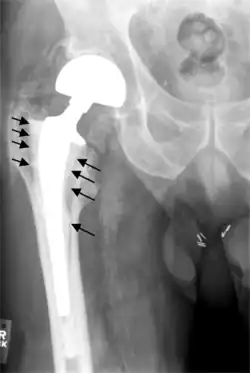

Loosening

On radiography, it is normal to see thin radiolucent areas of less than 2 mm around hip prosthesis components, or between a cement mantle and bone. These may indicate loosening of the prosthesis if they are new or changing, while areas greater than 2 mm may be harmless if they are stable.[45] The most important prognostic factors of cemented cups are absence of radiolucent lines in DeLee and Charnley zone I, as well as adequate cement mantle thickness.[46]